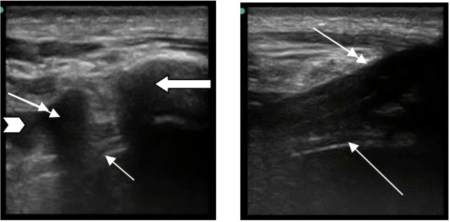

The rest of his FAST scan was negative, and we knew right then and there – left sided PNEUMOTHORAX!!!! We ordered for supplemental oxygen, and, of course, had a bedside Chest XRay done to complete the trauma evaluation:

So, there are some parts of the chest missing (namely, the lower portion and costophrenic angles) on this not-so-great picture from my iPhone, but the trauma team and I did not appreciate a pneumothorax on this image. And, it just goes to show those darn studies were right, US is more sensitive than a CXR. The patient went to CT and the OR got ready for his tib/fib, but my astute resident said that we should place a chest tube prior to the intubation as this could go bad and get worse (hello tension!) after intubation – and that would be just poor form – so, our trauma colleagues agreed and in went the chest tube after return from CT, The tube, by the way, I also confirmed by US guidance for its intrathoracic placement (of course, this is a new thing and a CXR also confirmed it): the tube (double arrow) seen as the hyperechoic walled (bright) structure with shadow posteriorly next to the larger rib in the transverse view (image on your left) and you can see it enter the pleural cavity in the longitudinal view (image on your right): The landmark picture was not the actual victim, just a very nice medical student who allowed us to place the tough tape for the picture. Gotta love them! Pretty cool stuff, I tell ya!!